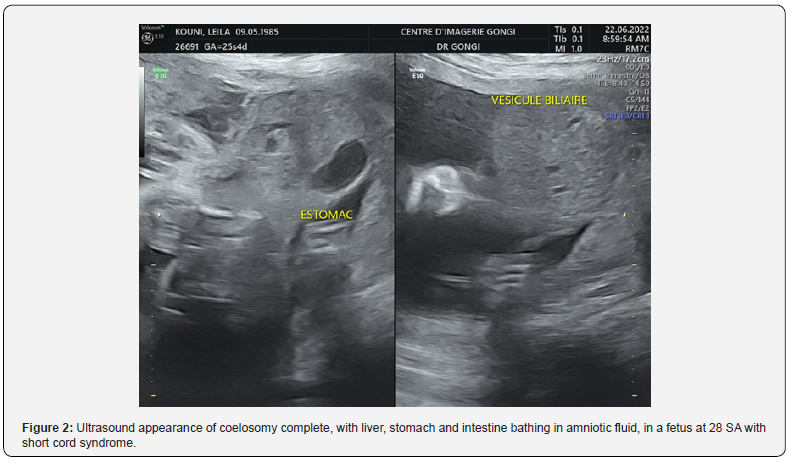

Obstetrical ultrasound revealed an evolving mono-fetal pregnancy, with amitotic fluid in diminished quantity, a cerebral floor without anomalies (Figure 1), a large coelosomycompléte, heart, liver and intestine bathed in amniotic fluid, (Figure 2) without individualization of the diaphragm, with anomalies of the spine (Figure 3) anomalies of the lower limbs, a right clubfoot. The fetus appeared to be attached to the placenta. An umbilical cord containing two arteries and a very short vein (Figure 4), The most likely diagnosis was short cord syndrome. After discussion with the parents and a psychological interview with the woman, the pregnancy was terminated. Macroscopic examination at birth revealed a male fetus weighing 500g, with a marked anterior complete coelosomy (heart, liver and intestine exteriorized). Narrow thorax. The spine is angulated, and the lower limbs are club-footed (Figure 4). The fetus was attached to the placenta by a very short 6 cm cord, with 2 arteries and one vein (Figure 5). The fetus was pathologically examined for other visceral malformations. However, all the ultrasound findings and macroscopic examination (Figure 6) enabled the diagnosis to be accepted.

An abnormally inseparable fetus (partially attached to the placenta). Absence of umbilical cord or very short cord. Large thoraco-abdominal wall defect (vast celosomy - coelosomy) in the form of a complete thoraco-abdominal evisceration not covered by a membrane. Sometimes the peritoneum fuses with the amnion (amnionperitonealsleeve). Defects of the thoraco-abdominal wall may be associated with diaphragmatic hernia or absence of the diaphragm; defect of the sternum and also cardiac malformations, in particular ectocardia (ectocardia - ectopiacordis). Visceral anomalies: intestinal atresia; renal malformations such as pyelectasis, renal agenesis, renal cystic dysplasia. Anomalies of the spine, such as scoliosis or kyphoscoliosis (sometimes with several points of angulation) and reduction anomalies of the spinal column (caudal regression). The neck is often elongated. Lower limb anomalies: club feet, reduction anomalies (absence of limbs or toes); polydactyly, syndactyly, arthrogryposis...